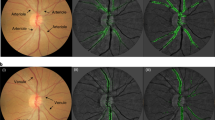

Traditionally, medical discoveries are made by observing associations, making hypotheses from them and then designing and running experiments to test the hypotheses. However, with medical images, observing and quantifying associations can often be difficult because of the wide variety of features, patterns, colours, values and shapes that are present in real data. Here, we show that deep learning can extract new knowledge from retinal fundus images. Using deep-learning models trained on data from 284,335 patients and validated on two independent datasets of 12,026 and 999 patients, we predicted cardiovascular risk factors not previously thought to be present or quantifiable in retinal images, such as age (mean absolute error within 3.26 years), gender (area under the receiver operating characteristic curve (AUC) = 0.97), smoking status (AUC = 0.71), systolic blood pressure (mean absolute error within 11.23 mmHg) and major adverse cardiac events (AUC = 0.70). We also show that the trained deep-learning models used anatomical features, such as the optic disc or blood vessels, to generate each prediction.